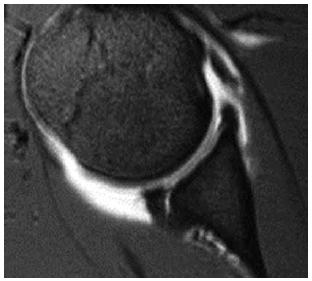

Paciente de 50 anos, sem comorbidades. Em exame de rotina, foi encontrada a imagem a seguir. Diante do achado da imagem, e com a opinião bem definida emitida pelo ultrassonografista no laudo, qual é a conduta mais adequada do nefro–urologista?